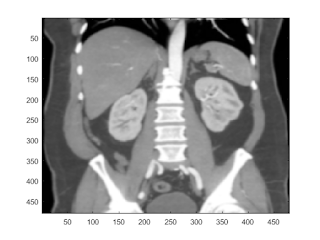

this matlab code provides some techniques and methods to view and identify organs of a CT image

The first method is to use histogram to segment the second method is to use color a CT image third method is filter.

% read a CT image I=imread('./Abdominal wall normal anat (8).png');

plot histogram of the image

subplot(311); % plot to ensure a correct image is loaded.

imhist(I)

subplot(3,1,2:3);

imshow(I);

colorbar